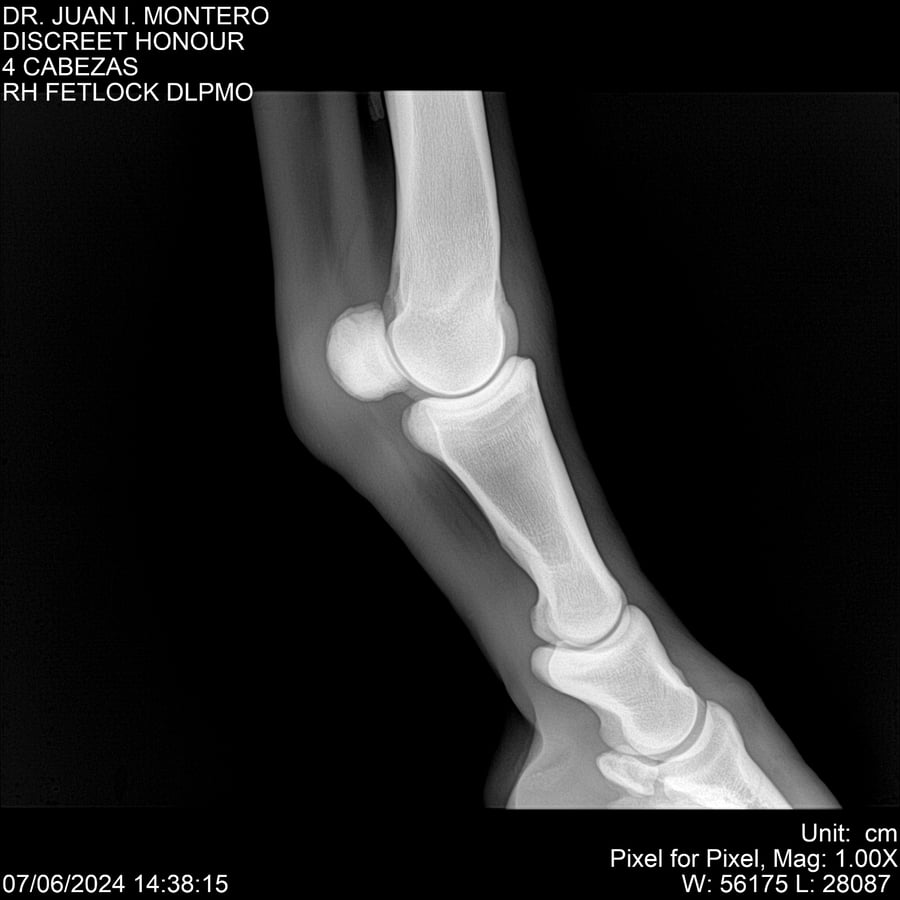

LOTE 6, DISCREET HONOUR 🔥 🔥 🔥 Lote Anterior Volver al remate Lote Siguiente Ficha Contacto Montevideo - Ficha del Lote Identificador: #281093 Categoría: Yeguarizos Montevideo - 82 Visualizaciones ClicData Contacto Empresa: Abelenda N. R., Walter Hugo Nombre*: Teléfono* : E-mail* : Mensaje Enviar Registrese gratis Este contenido Exclusivo está disponible sólo para usuarios registrados Ingresar